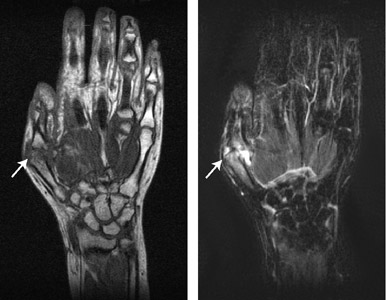

関節症状を訴え医療機関を受診したが、抗CCP抗体も含めて血清学的所見に異常がないため、経過観察されている症例は多く存在する。この症例は,3年前に右第2MCP関節の疼痛を自覚し,近医を受診した。しかし、身体所見,血清学的所見,単純X線写真上では異常を認めなかった。以後、症状が出現するたびに受診を続けていたがやはり、異常所見を認めなかった。

しかし、右第1MCP関節、左第5MCP関節・手関節の疼痛が継続して出現するようになったため、単純X線を撮影したところ,骨びらんを認めた。このため当科に紹介となり,コンパクトMRIの撮像を行った。当科受診時、CRP 0.17mg / dL、MMP-3 37.4ng / mL、RF 3IU / mL、CARF 1.2AU / mL、抗CCP抗体 4.5U / mL未満、抗核抗体 20倍未満と,血清学的には異常所見は認められなかった。しかし、コンパクトMRIを撮像したところ,患者の自覚症状の部位と一致して滑膜炎と骨びらんを認め、また,両手根間関節,左第2PIP関節でも滑膜炎を認めた(図1)。

a:T1強調画像(左手) b:STIR法(左手) |

c:T1強調画像(右手) d:STIR法(右手) |

図1 コンパクトMRI画像によるリウマチ早期診断例

左第5MCP関節,右第1MCP関節で,滑膜炎と骨びらんを認める。

また,両手根間関節,左第2PIP関節でも滑膜炎を認める。

・STIR:3D-STIR-FSE

TR/TEeff/TI = 1000 ms/70 ms/110 ms

Voxel size = 0.8 mm X 0.8 mm X 3.2 mm

Tacq = 6 min 30 sec

・T1WI:3D-GE

TR/TE/FA = 40 ms/5 ms/65 deg

Voxel size = 0.4 mm X 0.8 mm X 1.6 mmm

Tacq = 5 min 30 sec